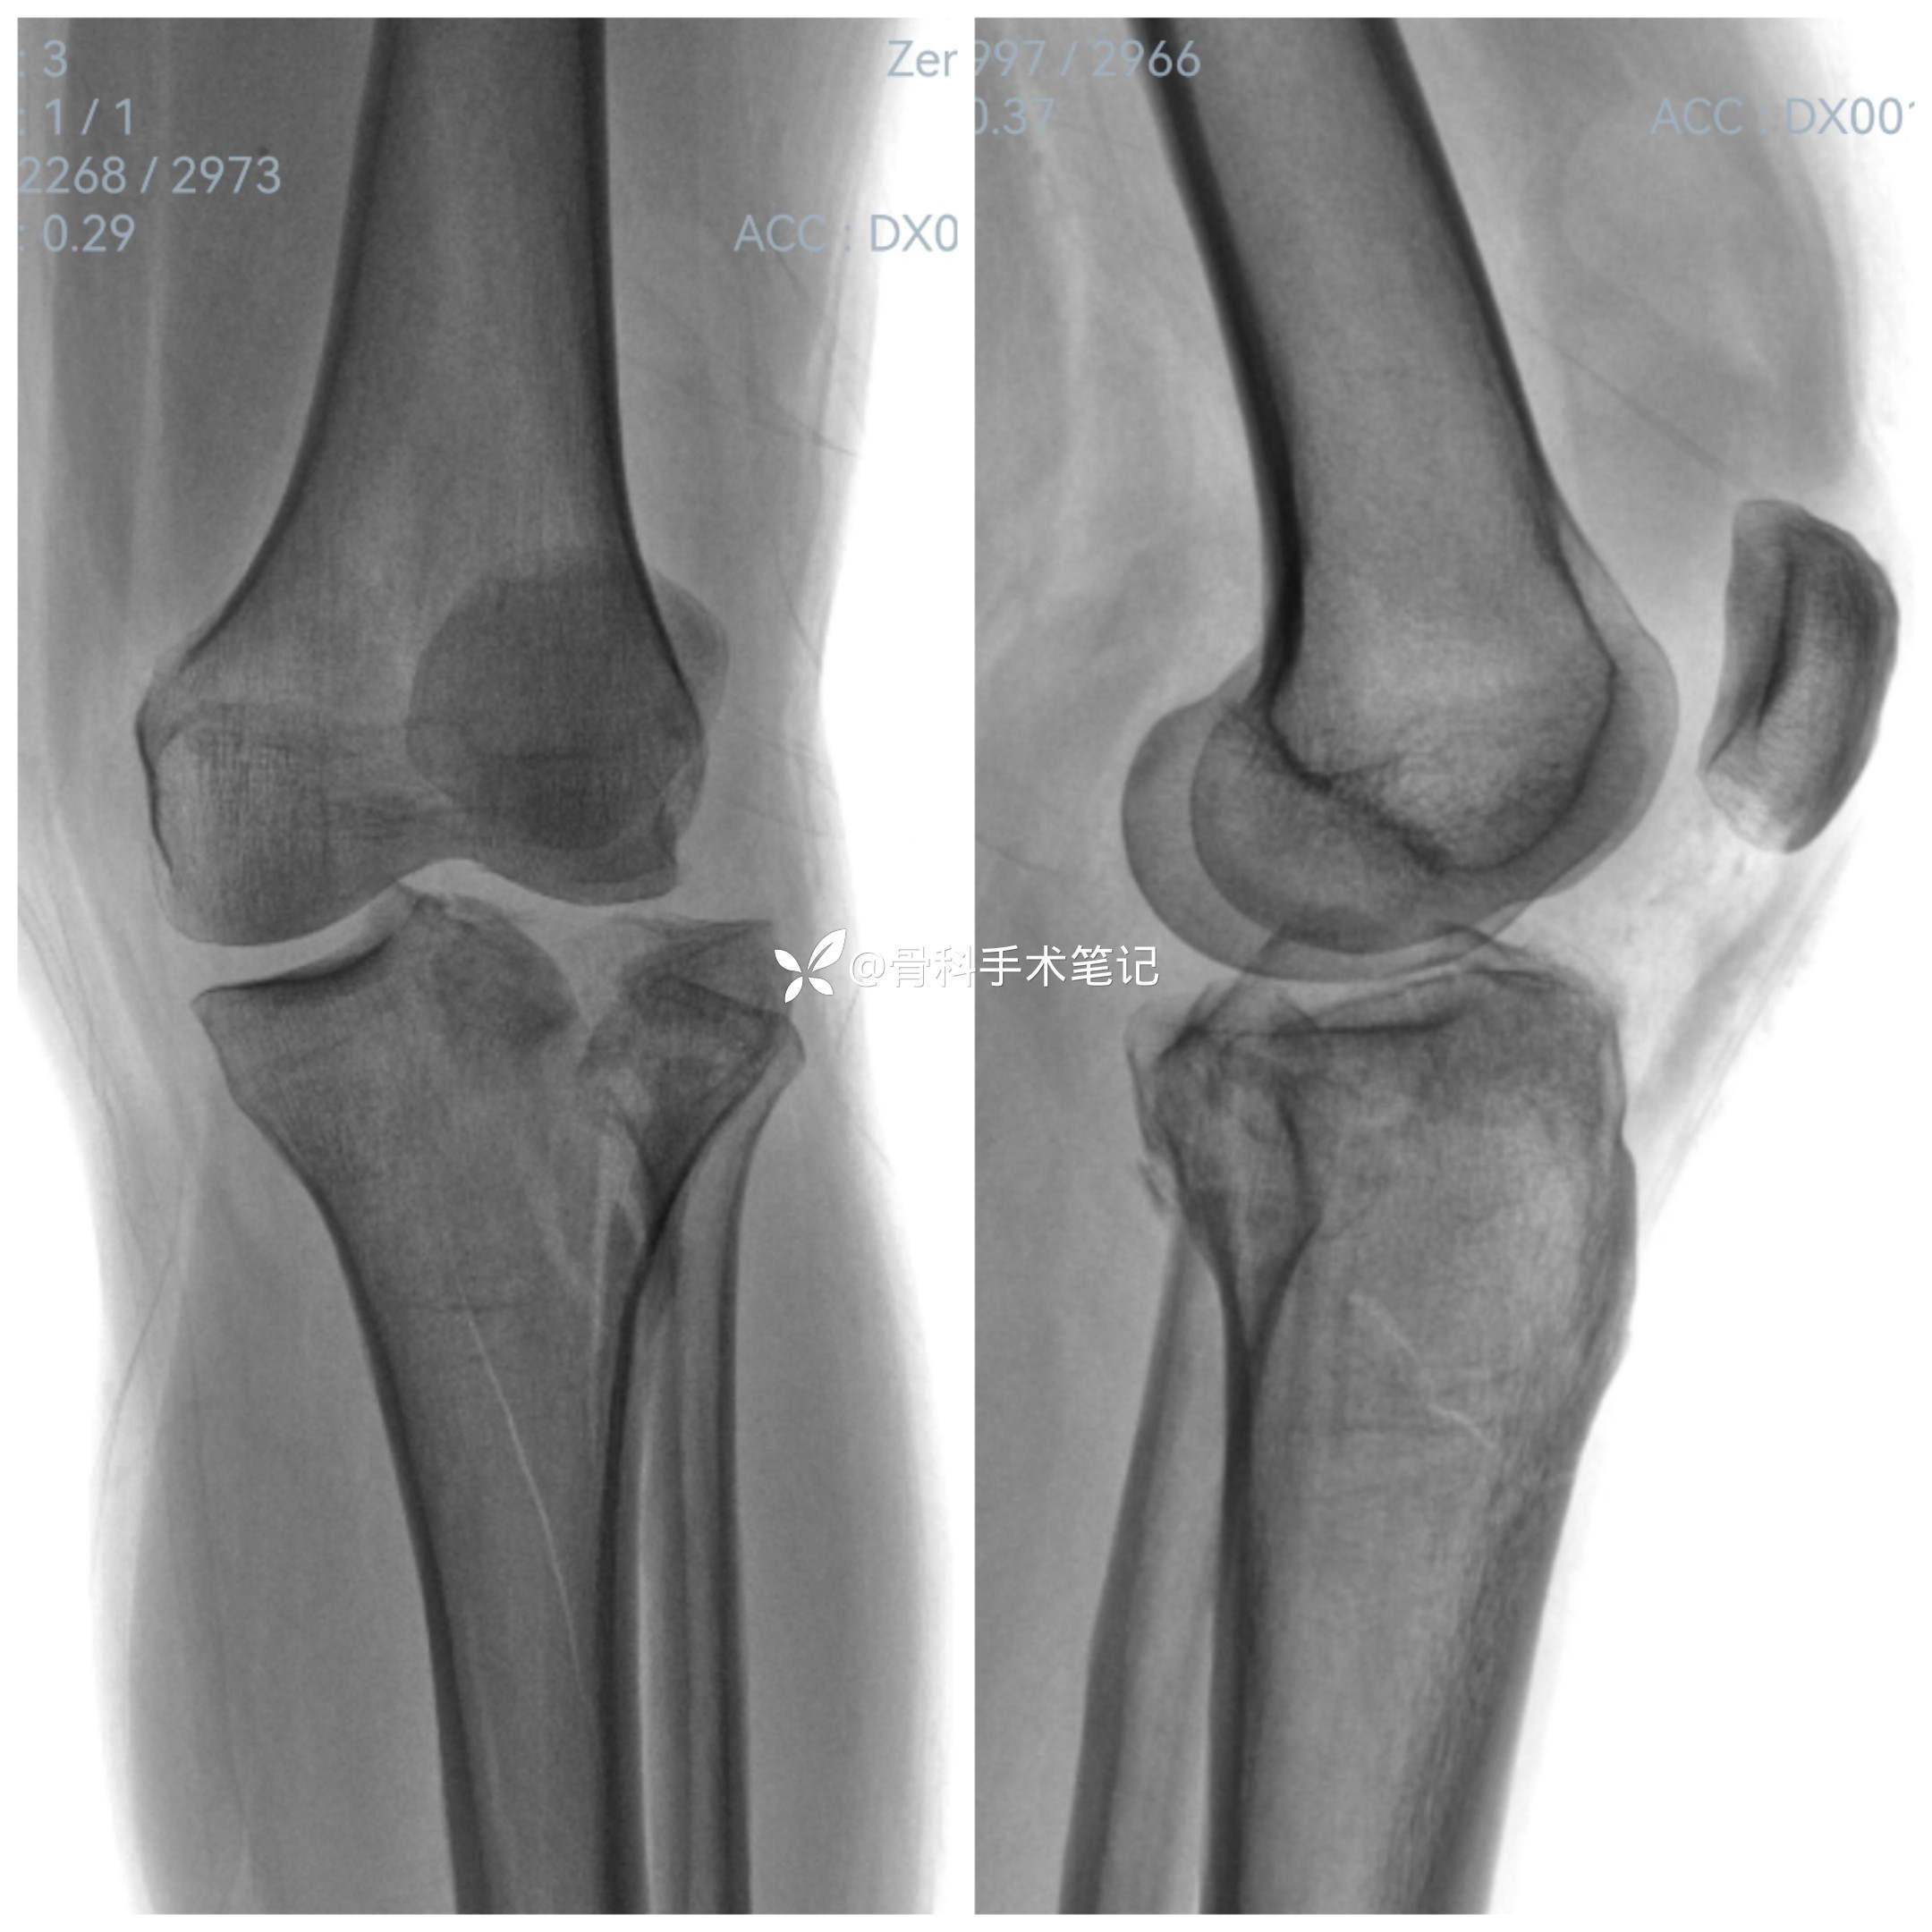

【患者信息】:女,50岁

【主诉】:高坠伤致左膝部疼痛伴活动受限3小时余。

【临床诊断】:1.左胫骨平台粉碎性骨折;2外侧半月板损伤。